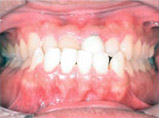

Before

Proceeding

After